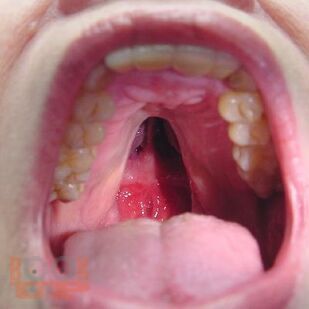

Пороки развития орофациальной области (клинико-морфологические аспекты)

В учебном пособии представлены клинико-морфологические аспекты пороков развития головы, лица и шеи, патолого-анатомическая диагностика пороков развития, особенности дифференциальной диагностики.

Учебное пособие «Пороки развития орофациальной области (клинико-морфологические аспекты)» составлено в соответствии с программами дисциплин «Патологическая анатомия – патологическая анатомия головы и шеи» для студентов, обучающихся по специальности «Стоматология», и «Патологическая анатомия, клиническая патологическая анатомия» для студентов, обучающихся по специальности «Педиатрия».